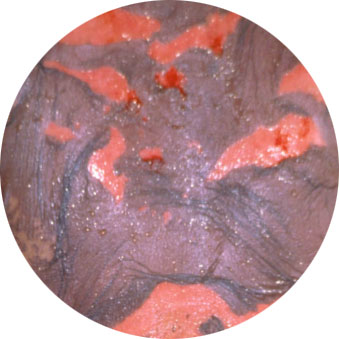

In FDE, single or multiple round to oval-shaped dark reddish patches develop in the same site or sites each time a particular drug is taken. Sometimes, there may be swelling, blistering or erosions in the affected areas. The lips or genitalia can occasionally be the only site of involvement in FDE. FDE usually occurs between 30 minutes to 8 hours after ingesting the culprit drug. The redness in FDE subsides with cessation of the culprit drug, but the dark patches can be persistent. There are many medications which can cause FDE, eg. tetracycline antibiotics.